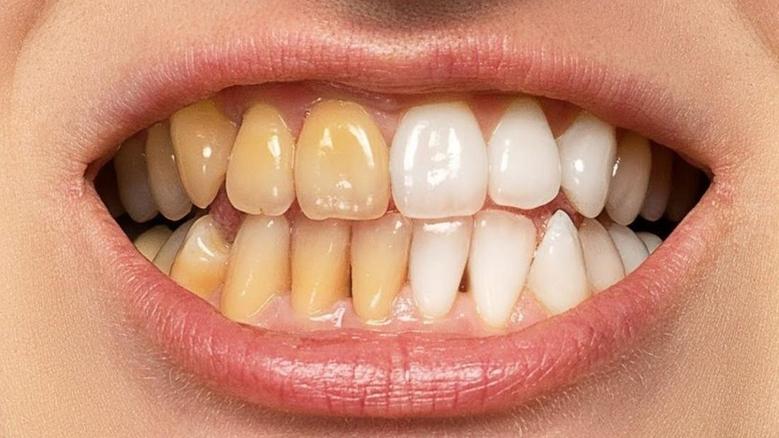

عادة ما يشير تغير لون الأسنان، حسبما ورد بموقع"كليفلاند" الطبي، إلى تغير لون الأسنان إلى تحول في لونها الطبيعي، إذ قد تبدو أقل بياضًا ولمعانًا، أو تظهر عليها بقع بألوان مختلفة مثل الأصفر، البني، وحتى الرمادي أو الأسود.

يحدث نتيجة تراكم الصبغات على سطح مينا الأسنان بفعل التعرض المستمر لأطعمة ومشروبات داكنة اللون مثل: الشاي والقهوة والنبيذ الأحمر، أو بسبب التدخين وسوء العناية بصحة الفم.

يبدأ من داخل السن ويصيب طبقة العاج، ويرجع غالبًا إلى إصابات الأسنان أو استخدام بعض أنواع الأدوية، لاسيما المضادات الحيوية كالتتراسيكلين خلال مرحلة الطفولة.